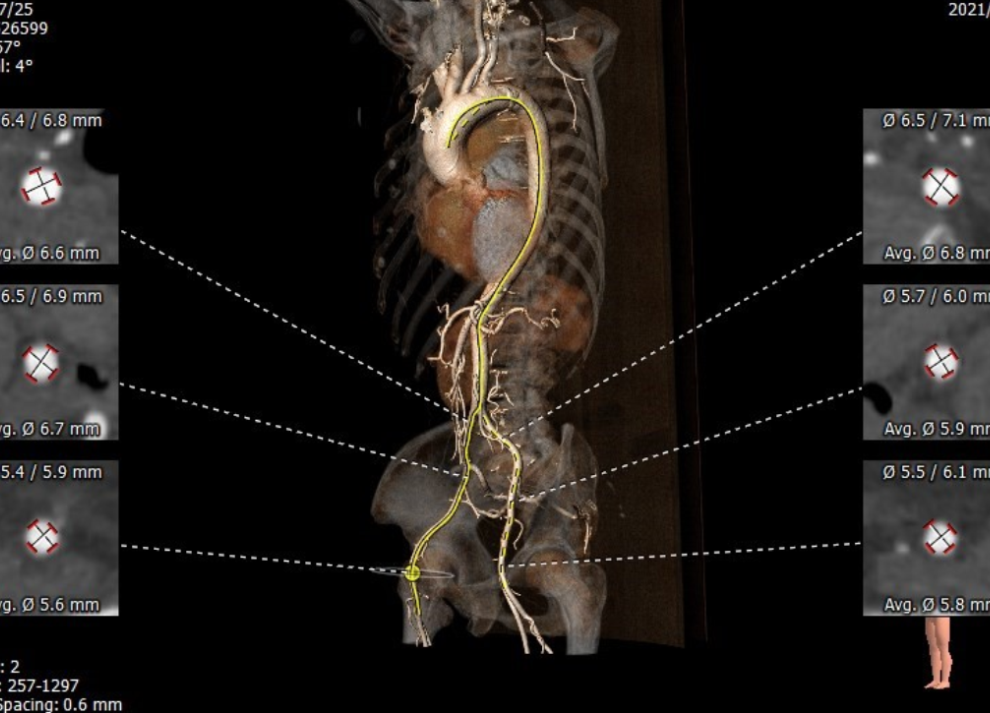

术前评估:

Annulus 22.6*27.5mm Perimeter=78.8mm

SOV 27.1*27.0*27.2mm

STJ 28.0*32.1mm

LVOT 21.5*28.7mm Perimeter=78.5mm

Ascending Aorta 38.7*40.1m

内径符合TAVI要求

该患者CT特点为:

功能性二叶瓣,左右融合,钙化集中于无冠窦,长条状钙化自瓣上延续至二尖瓣前叶,冠脉开口高度可,腹主动脉至髂动脉多发钙化,内径可,拟右股动脉入路,22mm球囊扩张,植入VitaFlow 27。